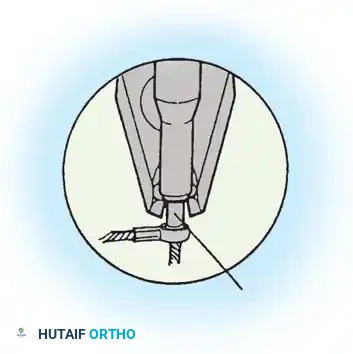

The Moe Technique (Thoracic Spine)

The Moe technique is a highly effective method for achieving intra-articular arthrodesis in the coronally oriented thoracic facet joints.

Fig. 38-26: The Moe technique of thoracic facet fusion, demonstrating the creation of hinged bone flaps.

- Expose the spine fully to the tips of the transverse processes.

- Using a sharp osteotome or Cobb gouge, begin a cut over the cephalad articular process at the base of the lamina.

- Carry this cut along the transverse process almost to its tip. Bend this cortical fragment laterally so it lies between the transverse processes, ideally leaving it hinged on its lateral periosteal attachment to preserve local vascularity.

- Thoroughly denude all articular cartilage from the superior articular process using a sharp curet.

- Make a secondary cut in the superior articular facet, working medially to laterally, producing another hinged fragment.

- Pack the resulting intra-articular defect tightly with cancellous bone graft.